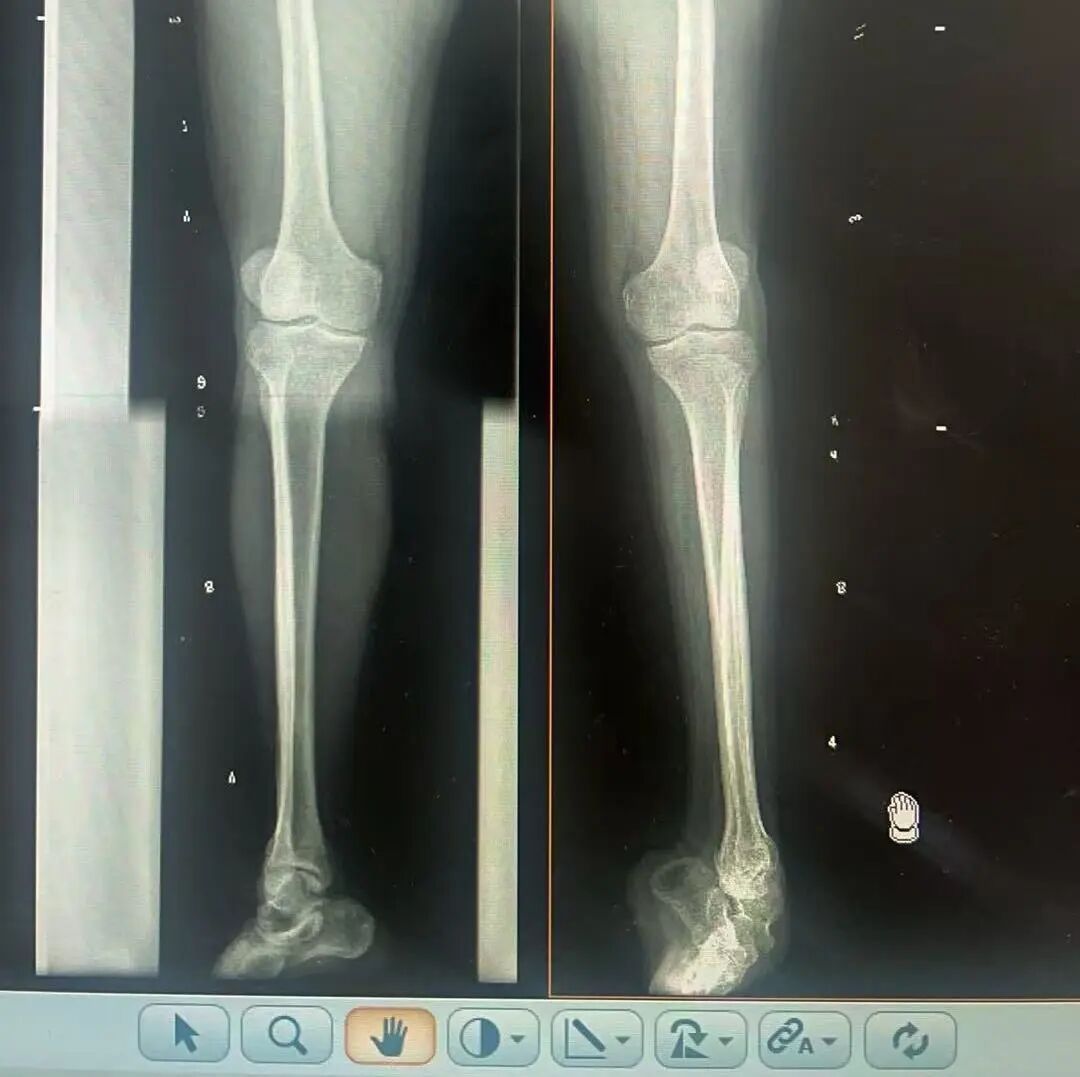

術(shù)前X光片 VS 術(shù)后治療效果

骨科隨即為陽先生進(jìn)行了全面的檢查。診斷明確而復(fù)雜:陽先生患有脊髓灰質(zhì)炎后遺癥、左踝馬蹄內(nèi)翻足、骨盆傾斜……面對這張沉甸甸的診斷書,由肢體功能重建顯微修復(fù)學(xué)科組長鄭群龍所帶領(lǐng)的醫(yī)療團隊沒有畏懼,“這是一個家庭38年的堅守與期盼,我們必須全力以赴”

針對陽先生的復(fù)雜情況,鄭群龍醫(yī)師團隊制定了詳盡的手術(shù)方案:左踝關(guān)節(jié)融合+馬蹄足畸形矯正+跟腱延長+外固定架固定術(shù)。手術(shù)的核心,正是伊里扎洛夫技術(shù)。這項技術(shù)如同精密的“時空建筑學(xué)”,通過微創(chuàng)安裝環(huán)形外固定架,前足-后足安裝鋼環(huán),再將足的鋼環(huán)與脛骨的固定鋼環(huán)在踝關(guān)節(jié)前、后、左、右用帶關(guān)節(jié)的螺紋桿連接,由此構(gòu)建成一個能體外牽拉調(diào)控的三維立體構(gòu)型,在術(shù)后進(jìn)行精準(zhǔn)、緩慢的調(diào)整,一寸一寸逐步將畸形的骨骼、軟組織恢復(fù)到正常位置。

9月1日,在全麻狀態(tài)下,陽先生接受了伊里扎洛夫外固定架安裝術(shù)。鄭群龍團隊在陽先生左足足踝部植入克氏針及半針,安裝外固定架,通過支架的機械結(jié)構(gòu)對馬蹄內(nèi)翻畸形進(jìn)行緩慢、持續(xù)的牽拉矯正。術(shù)后,鄭群龍團隊反復(fù)指導(dǎo)訓(xùn)練陽先生父子進(jìn)行外固定架的日常調(diào)試,按照預(yù)定計劃每日調(diào)整螺桿,逐漸糾正足部畸形,并配合專業(yè)的康復(fù)訓(xùn)練,包括踝關(guān)節(jié)主動及被動活動、下肢肌力訓(xùn)練等項目促進(jìn)陽先生腿部肢體功能恢復(fù),預(yù)防肌肉萎縮及關(guān)節(jié)僵硬。